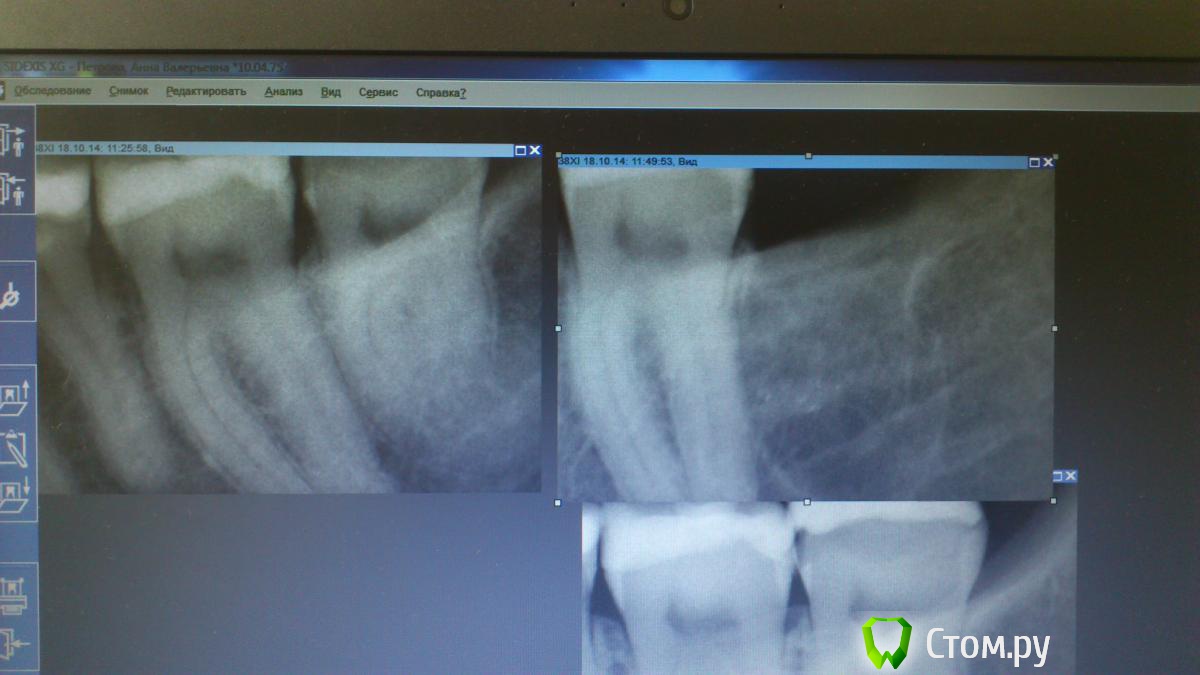

faity Опубликовано 7 августа, 2014 Поделиться Опубликовано 7 августа, 2014 а это вечернее, за качество фото извиняюсь, мертвый был совсемэта штука была анкилозированна и постоянно ломалась. соответсвенно правая верх, левая низ 1 Ссылка на комментарий